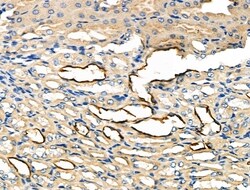

Invitrogen™ Glypican 3 Polyclonal Antibody

Antibody detects endogenous levels of total GPC3.

| Applications | Immunohistochemistry (Paraffin), Western Blot, Immunocytochemistry, Western Blot |